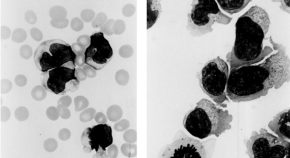

A new mouse model is developed in which haematopoietic malignancies are caused by genetic changes in the microenvironment of blood cells. Deletion in bone progenitor cells of Dicer1, a gene involved in microRNA processing, leads to a myelodysplastic syndrome-like phenotype which can progress to leukaemia. Deregulation of Sbds, which is mutated in human Schwachman–Bodian–Diamond syndrome, may be involved in this process.